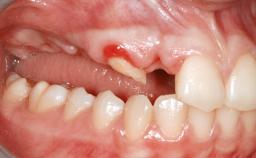

Le Fort I Interpositional Graft and Mandibular Sandwich Osteotomy for Maxillofacial Rehabilitation after Severe Periodontitis

A 47-year-old woman who had suffered from aggressive periodontitis requiring a number of periodontal interventions over more than 10 years was referred by her general dental practitioner and periodontologist for bone augmentation and implant therapy. Her failing dentition had already been scheduled for extraction. The patient expressed a desire for implant-supported fixed restorations and esthetic improvement of her lower face. She had agreed to consult with a maxillofacial surgeon after the referring dentist had suggested bone augmentation. An initial examination by the maxillofacial surgeon revealed mobility of all residual teeth in a patient who was very unhappy with the function of her removable partial dentures. Due to periodontally migrated flaring teeth and loss of occlusal support, the vertical dimension of occlusion was dramatically reduced. The patient was displeased with her lower face because of deepened nasolabial, commissural, and supramental folds.

Bone Volume Horizontally and vertically sufficient Horizontally deficient Deficient vertically or deficient vertically AND horizontally

Bone Volume Deficient vertically or deficient vertically AND horizontally